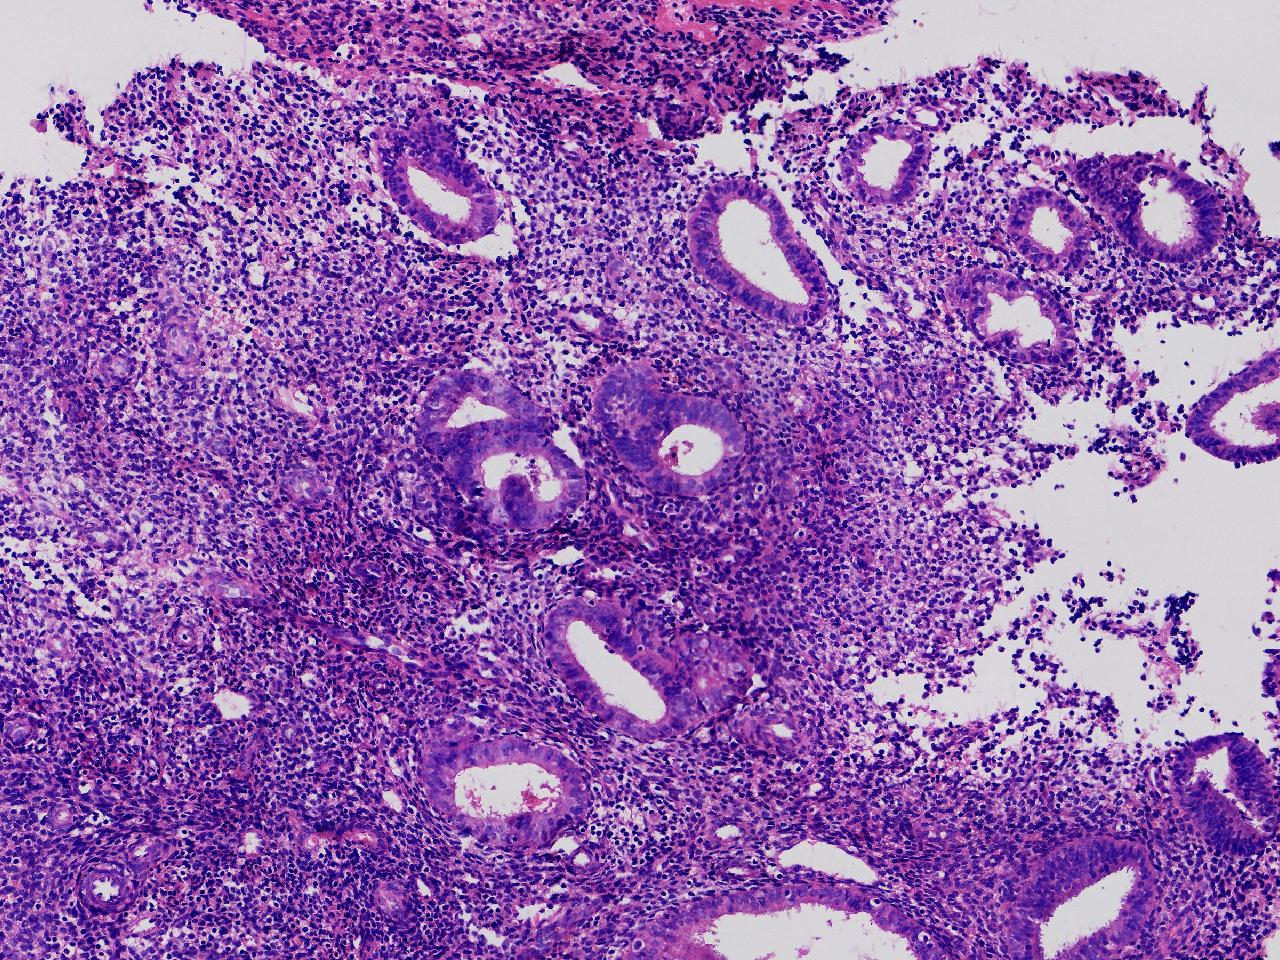

请教诊断。局灶够不够非典?

阴道不规则出血20余日,彩超示:内膜线居中,厚15毫米。

子宫内膜

灰粉色不整形软组织多块,3X2X1厘米。

不够非典

有输卵管上皮化生,感觉不够非典。